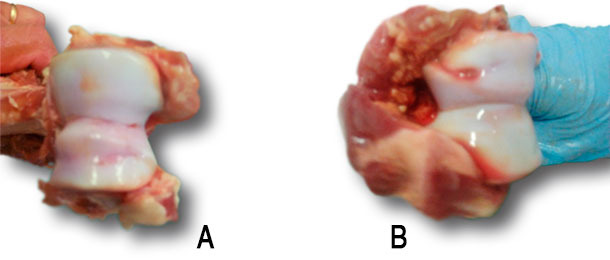

L’ostéochondrose est une cause connue de faiblesse des extrémités chez les truies qui est associé souvent avec les boiteries et l’élimination prématurée. Cependant, il n’en est pas toujours ainsi. Elle comporte un dommage irréversible du cartilage articulaire de l’os sous-jacent des articulations et on la rencontre plus fréquemment dans l’articulation du coude. L’ostéochondrose est difficile à identifier chez les truies vivantes, à la différence des lésions des extrémités et des onglons puisqu’il n’y a pas d’indicateurs externes fiables.

Ostéochondrose du condyle huméral (articulation du coude): A) cartilage sans irrégularité, et B) cartilage avec une grave irrégularité